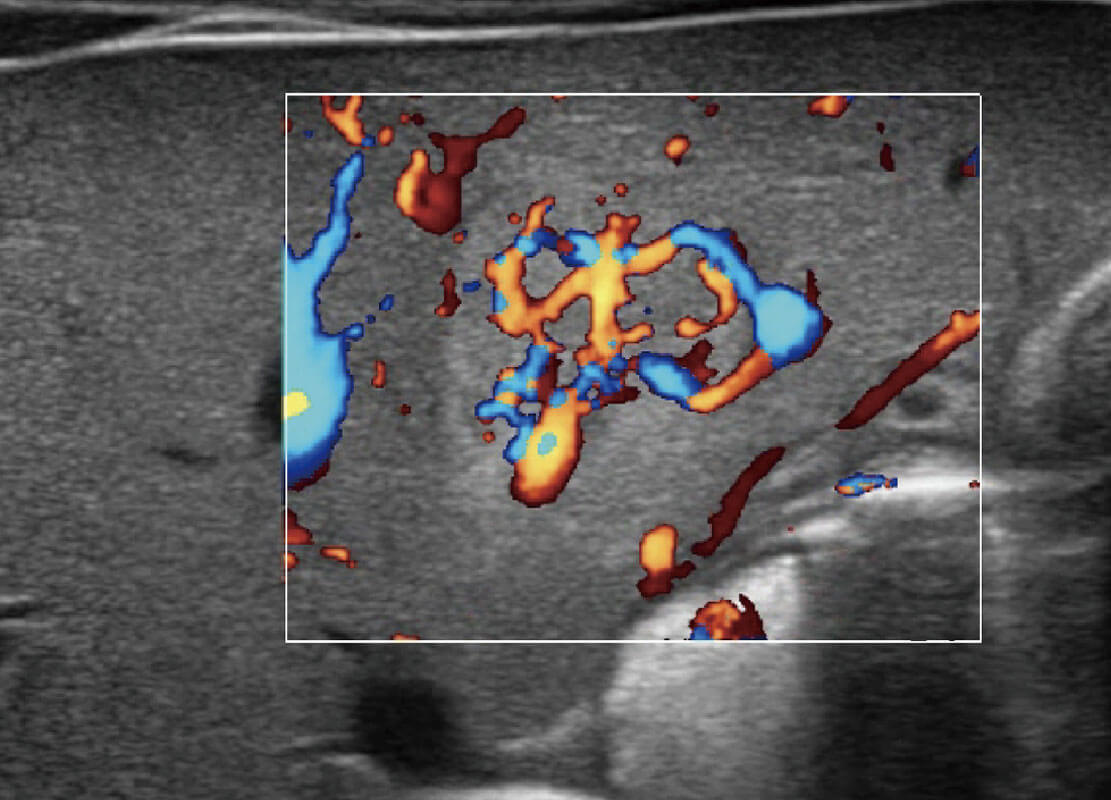

新生儿肝血管癌